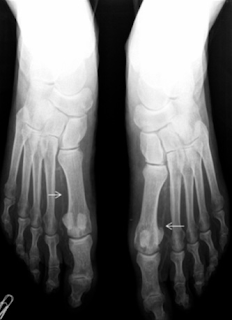

| Arteria pedia calcificada. Hallazgo bilareral |

Alteraciones en tejido óseo

- Infección ósea (osteomielitis)

- Cambios articulares y óseos neurotróficos, con atrofia, reabsorción y necrosis ósea eventualmente.

- Osteopatía diabética

- Neuroartropatia